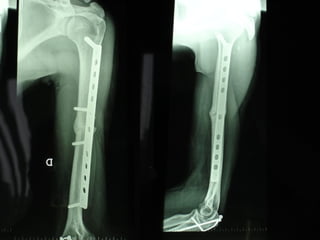

Il trattamento delle fratture distali di femore con la placca NCB a stabilità angolare poliassiale A.Luzzati , F.Feraboli   ( Divisione di Ortopedia – Azienda Ospitaliera di Cremona Responsabile : Dott. Alessandro Luzzati )

Dal Gennaio 2000 al Febbraio 2006 abbiamo trattato 167 fratture chiuse  con placca percutanea  in 164 pazienti :  27 lesioni diafisarie di gamba, 12 piloni tibiali ,  11 fratture prossimali di tibia, 36 fratture sovracondiloidee di femore, 17 fratture diafisarie di femore, 43 fratture metaepifisarie prossimali di omero, 21 diafisarie d’omero.  156 guarigioni 8 fallimenti

INDICAZIONI COMUNI Fratture sovracondiloidee Fratture intercondiliodee Fratture diafisarie distali PARTICOLARI Fratture con grave osteoporosi Fratture periprotesiche

VANTAGGI CHIRURGIA MININVASIVA Mini Open Inserimento della placca sottocutaneo per scivolamento Viti percutanee Preservazione dei tessuti molli Ridotto danno vascolare Rapida ripresa funzionale

Conclusioni Riduzione  anatomica Minimo trauma chirurgico Corretto equilibrio fra elasticità e stabilità Precoce mobilizzazione